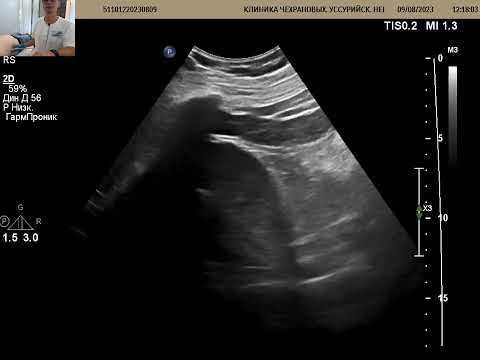

УЗИ почек при почечной колике. Уретерогидронефроз, нефролитиаз.